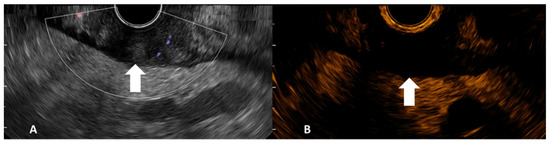

After TNM EUS staging, the CHI-EUS examination was performed. A low mechanical index (dynamic wide-band contrast harmonic imaging mode) of 0.2 was chosen. The tumor was properly examined in conventional gray-scale B-mode until the desired area for examination was highlighted (Figure 1). For example, in the case of a tumor causing gastric outlet obstruction, only the proximal side of the lesion was assessed. An intravenous bolus injection of 4.8 mL of a second-generation contrast agent (SonoVue, Bracco, Milan, Italia) was injected followed by a 5 mL 0.9% sodium chloride flush. CHI-EUS examinations (T0-T120s) were assessed in real-time and recorded on a local HDD for later system analysis. The contrast enhancement pattern was noted.

Figure 1. Gray-scale B-mode EUS image side-completed with Doppler mode (A) and contrast harmonic EUS image side (B) of gastric adenocarcinoma (tumor indicated by arrows).